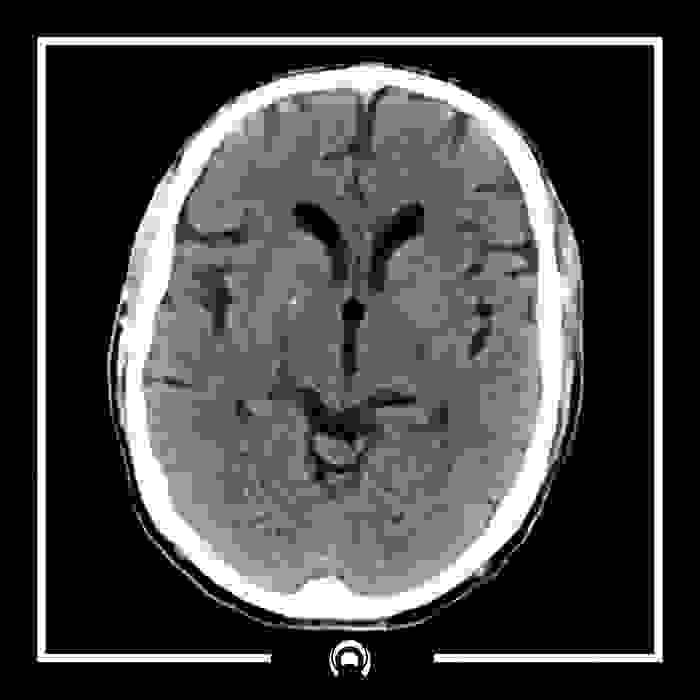

Section image

Tomografía Computada de Cráneo

Esencial para detectar condiciones neurológicas,

como hemorragias cerebrales, tumores

y fracturas craneales.

Saber mas...